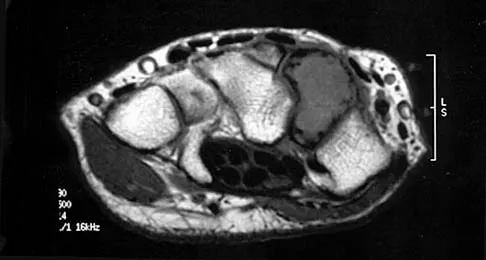

A 12-year-old girl who plays softball has chronic lateral hindfoot aching pain that is aggravated by weight-bearing activity. She reports that the pain has recurred after initial improvement with cast immobilization, and it continues to limit her overall level of activity. Radiographs are seen in Figures 40a through 40c. What is the most appropriate surgical treatment?

Explanation